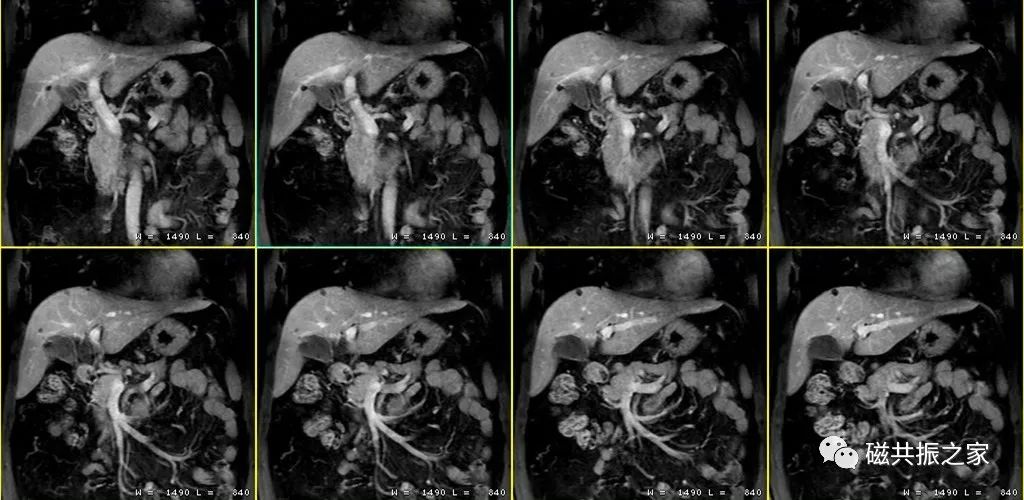

冠状位:冠状位平衡期/延迟期增强补充序列

在横轴位及矢状位上定位,范围包括整个肝脏及病变范围。

大范围的冠状位增强序列有助于对血管、胆管、十二指肠区域以及周围受累情况的评估,